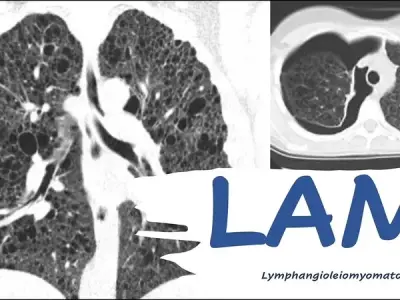

Lymphangioleiomyomatosis (LAM) is a rare lung disease affecting women. Learn its causes, key symptoms like shortness of breath, and treatments like sirolimus.